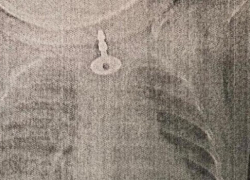

Медики Анапы рассказали корреспондентам местного издания, как вирусы гриппа или коронавирусной инфекции приводят к респираторным заболеваниям разной степен...